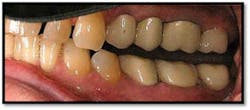

UR/LR Pre TxThe tissues around the posterior crowns are almost bluish in color(above left)UL/LL Pre Tx: